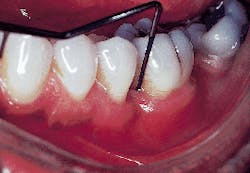

Figure 6 demonstrates a periodontal probe placed on the mesial aspect of the molar. A probing depth of less than 3mm`s can be seen. The original probing depth was 8mm`s.

Figure 6: A clinical photograph of tooth #19 at six months. Probing depths on the mesial aspect of this tooth were less than or equal to 3mm`s.